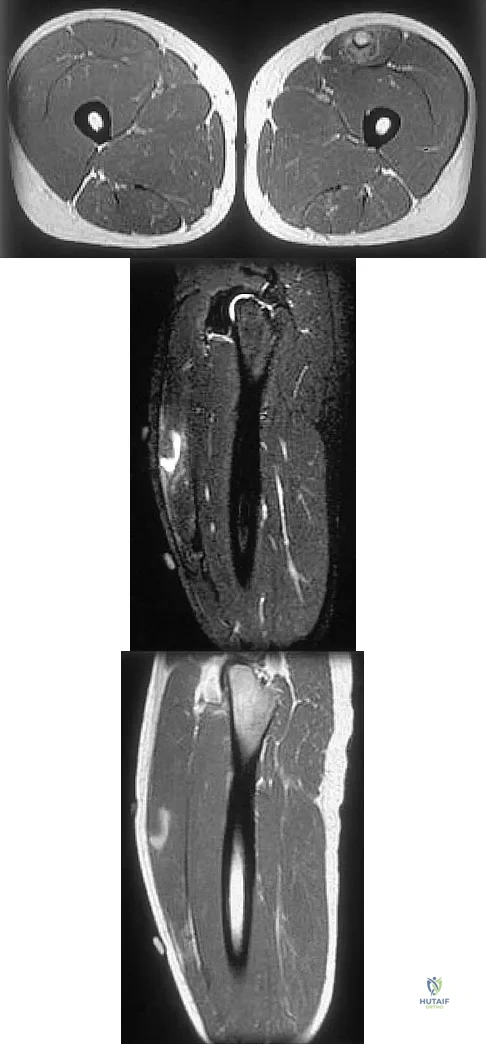

Figures 34a through 34c show an axial proton density (spin echo long TR, short TE) image, a sagittal inversion recovery (STIR) image, and a sagittal T1-weighted (short TR, short TE) image of the left thigh. What is the most likely diagnosis?

Explanation

Figures 35a and 35b show the axial T2-weighted and coronal T1-weighted MRI scans of a patient who has enlargement of the right thigh. What is the most likely diagnosis?

Explanation